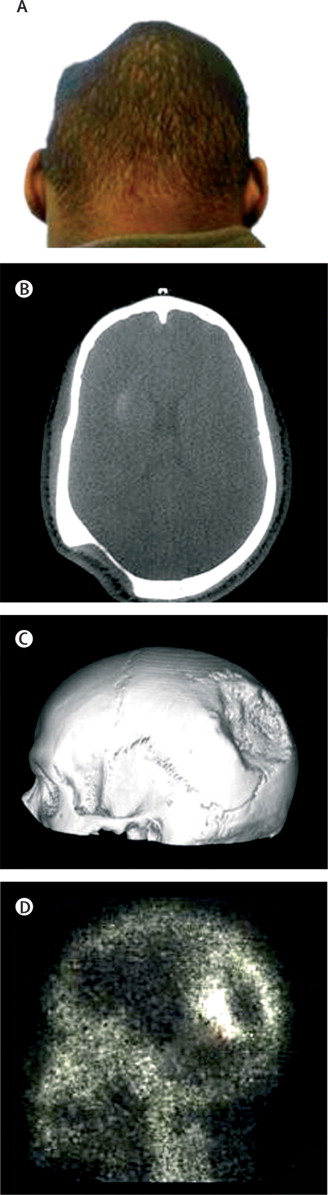

Пациент 40 лет, длительное время не посещавший медицинских учреждений, обратился в Hospital de la Salpetriere, (Франция) с жалобами на наличие «вмятины» на волосистой части головы (изображение А).

При КТ головы в костях черепа определялась значительных размеров область деструкции костной ткани с достаточно четкими контурами (изображение В – томограмма в горизонтальной плоскости; изображение С – КТ черепа с трехмерной реконструкцией). При сцинтиграфии костей с технеций99-метилен дифосфатом в краевых зонах очага деструкции отмечалась повышенная метаболическая активность (изображение D).

Данные изменения соответствуют признакам болезни Горхема – редкого идиопатического состояния, при котором в одной или нескольких костях развиваются процессы деструкции и замещения костной ткани соединительной или сосудистой тканями. Болезнь Горхема ребер или грудных позвонков может приводить к развитию хилоторакса и летальным исходам вследствие дыхательной недостаточности. В качестве основных методов лечения применяется лучевая терапия и хирургические вмешательства.